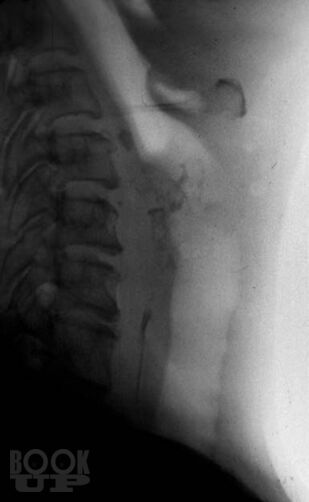

Книга П.В. Власова посвящена традиционным методам рентгенологического исследования пищеварительного тракта. В последние 20 лет периодическая печать заполнена публикациями, посвященными новым, модным и актуальным вопросам применения новейших методов лучевой диагностики, таких как ультрасонография, компьютерная и магнитнорезонансная томография. Между тем как подавляющее большинство рентгенологов в своей практической работе используют традиционные методы рентгенологического исследования, являющиеся базовыми, первичными в клинической диагностике различных заболеваний.